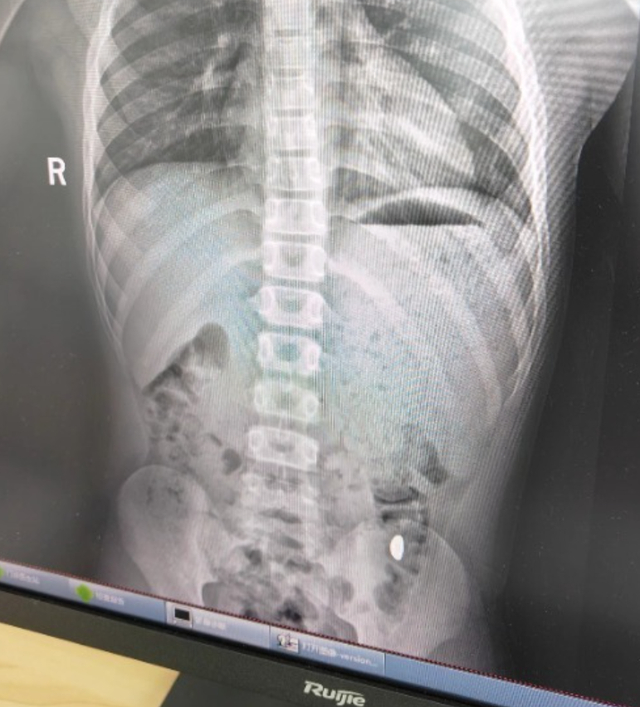

昆山市第五人民医院门诊病历单显示,患儿5天前误吞约10克黄金,其间解两次大便未发现,目前无腹痛、呕吐等症状,诊断结果显示胃内有异物。

右下加亮点为金豆。